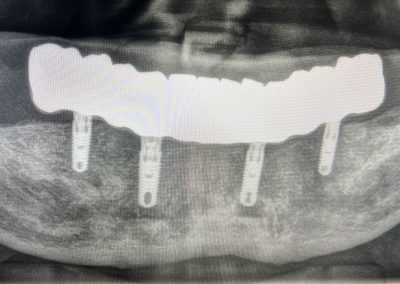

Protesi completa

su impianti all on six e all on four

Il dottor Filippo Marianelli e la sua equipe eseguono interventi di implantologia di alto livello grazie ad una tecnica all’avanguardia come la “All on Six” e la “All on Four”.

La tecnica si avvale di 4 o 6 impianti dentali inseriti nell’arcata superiore o inferiore che fungono da sostegno ad una protesi fissa.

L’implantologia All on Six e All on Four nascono per ovviare alla scelta obbligata della dentiera e finalmente poter contare su denti fissi, che garantiscano stabilità e comfort a lungo nel tempo. Durante questo intervento, lo specialista avviterà le protesi direttamente sugli impianti osteointegrati, inseriti sull’osso residuo.